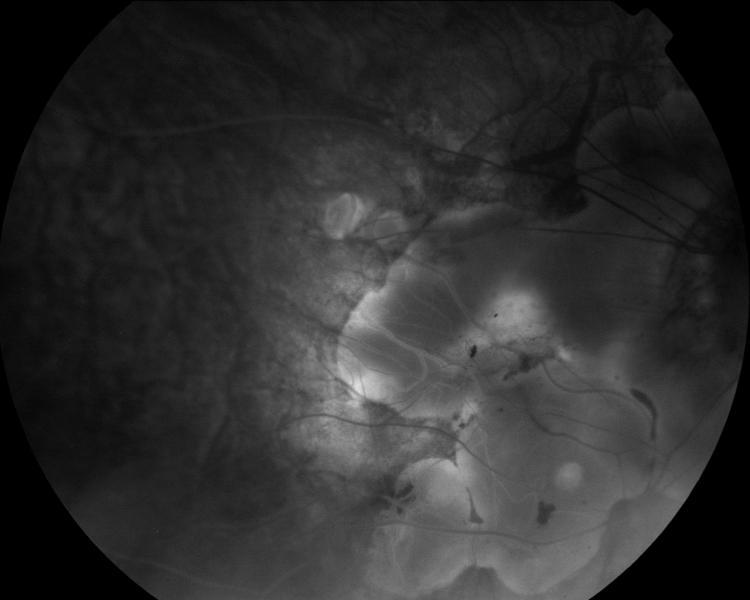

IM000036.JPG